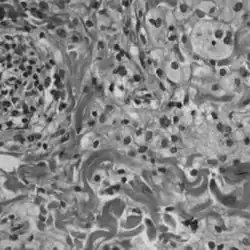

| Histopathology slide of Erdheim-Chester disease | |

A definitive diagnosis of ECD is made when CD68-positive, CD1a-negative histiocytes are identified in a biopsy specimen.[2] ECD is marked by the buildup of foamy histiocytes and occasional Touton giant cells in a fibrous tissue background. Tissue samples show xanthomatous or xanthogranulomatous infiltration by lipid-laden histiocytes.[8] Lymphoplasmacytic infiltrates may be present but are usually sparse. The histiocytes in ECD typically show similar markers to reactive histiocytes, except when the BRAF V600E mutation is found. Classic signs, like foamy histiocytes, may not always be visible and could instead show general inflammation and fibrosis.[9]

Immunohistochemical staining (IHC) can assist in diagnosing and classifying ECD versus other histiocytic neoplasms such as LCH. Using BRAF V600E-specific antibodies in IHC testing provides high accuracy for diagnosing the former.[9] Unlike LCH, ECD does not stain positive for S-100 proteins or Group 1 CD1a glycoproteins, and electron microscopy of cell cytoplasm does not disclose Birbeck granules.[8] More sensitive methods like pyrosequencing or digital droplet polymerase chain reaction may be helpful if aforementioned methods return with inconclusive results.